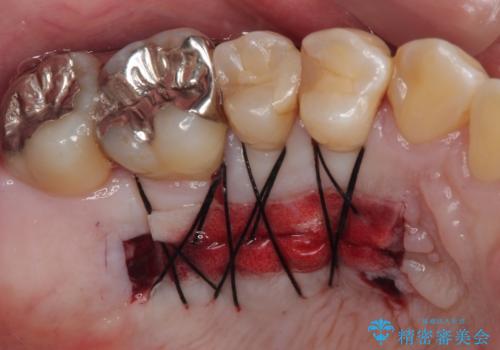

歯肉退縮に対して、上顎からの結合組織移植術(CTG)により、歯根の被覆を行うとともに、歯肉の厚みを増すことで将来の退縮リスクを抑制することとしました。

被覆量が不十分の場合には、追加で手術を行うことで患者様の了解を得ました。

一度の処置で大幅に露出部の被覆に成功しましたが、更なる厚みと被覆を希望されて2回目の処置を行いました。

歯根部周辺の歯肉が非常に分厚くなり、今後の退縮リスクが大きく軽減されました。